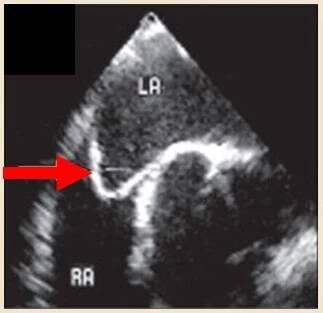

Aneuryzma atriálního septa na TEE

Aneurysma je medicínský výraz pro rozšíření neboli výduť dutého orgánu ( z řeckého aneurynein = otvírat). Nejčastěji se vztahuje k tepnám, nebo stěně srdeční komory. Aneurysma srdce může vzniknout po rozsáhlejším infarktu myokardu. Poškozená svalovina srdce se zhojí jizvou, která se vyklene tlakem krve v pracujícím srdci. Zhoršuje vypuzovací funkci srdce – stěna vyklenutí se nestahuje. Může se vyplnit krevní sraženinou, která ohrožuje nemocného embolizací. Aneurysma tepny je důsledkem vrozené… Wikipedie